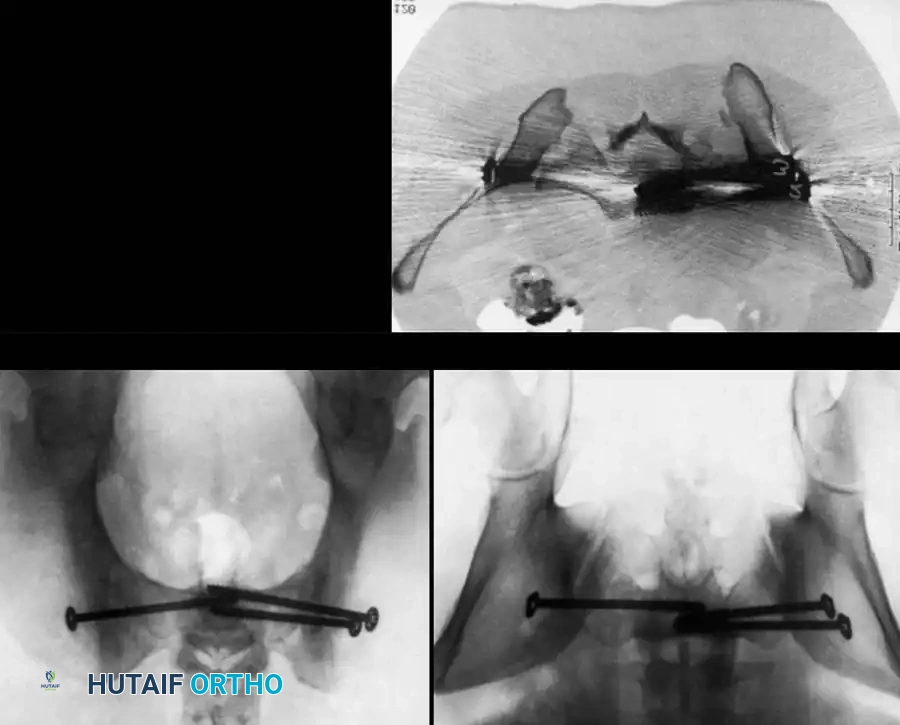

3. Percutaneous Sacroiliac (SI) Screws (Posterior Ring)

The gold standard for posterior ring fixation in appropriately selected patients.

* Indications: Sacral fractures, SI joint disruptions, crescent fractures.

* Technique: Performed under strict fluoroscopic guidance (Inlet, Outlet, and Lateral sacral views).

* Trajectory: The guide wire is advanced from the lateral ilium, across the SI joint, into the S1 (or S2) vertebral body.

* Safety Corridors: The surgeon must possess an intimate understanding of sacral dysmorphism. The "safe zone" is bounded by the sacral neural foramina inferiorly, the spinal canal posteriorly, and the sacral ala anteriorly.

Pitfall: Failure to recognize a dysmorphic sacrum (characterized by upper sacral segment elevation, non-recessed alae, and oblique neural foramina) can lead to catastrophic L5 nerve root injury or vascular penetration during SI screw placement.

Image

4. Posterior Tension Band Plating

For comminuted sacral fractures or when percutaneous corridors are unsafe, open reduction and posterior tension band plating (or lumbopelvic fixation) may be required. This involves placing plates across the posterior ilium to the sacrum, effectively recreating the posterior ligamentous tension band.